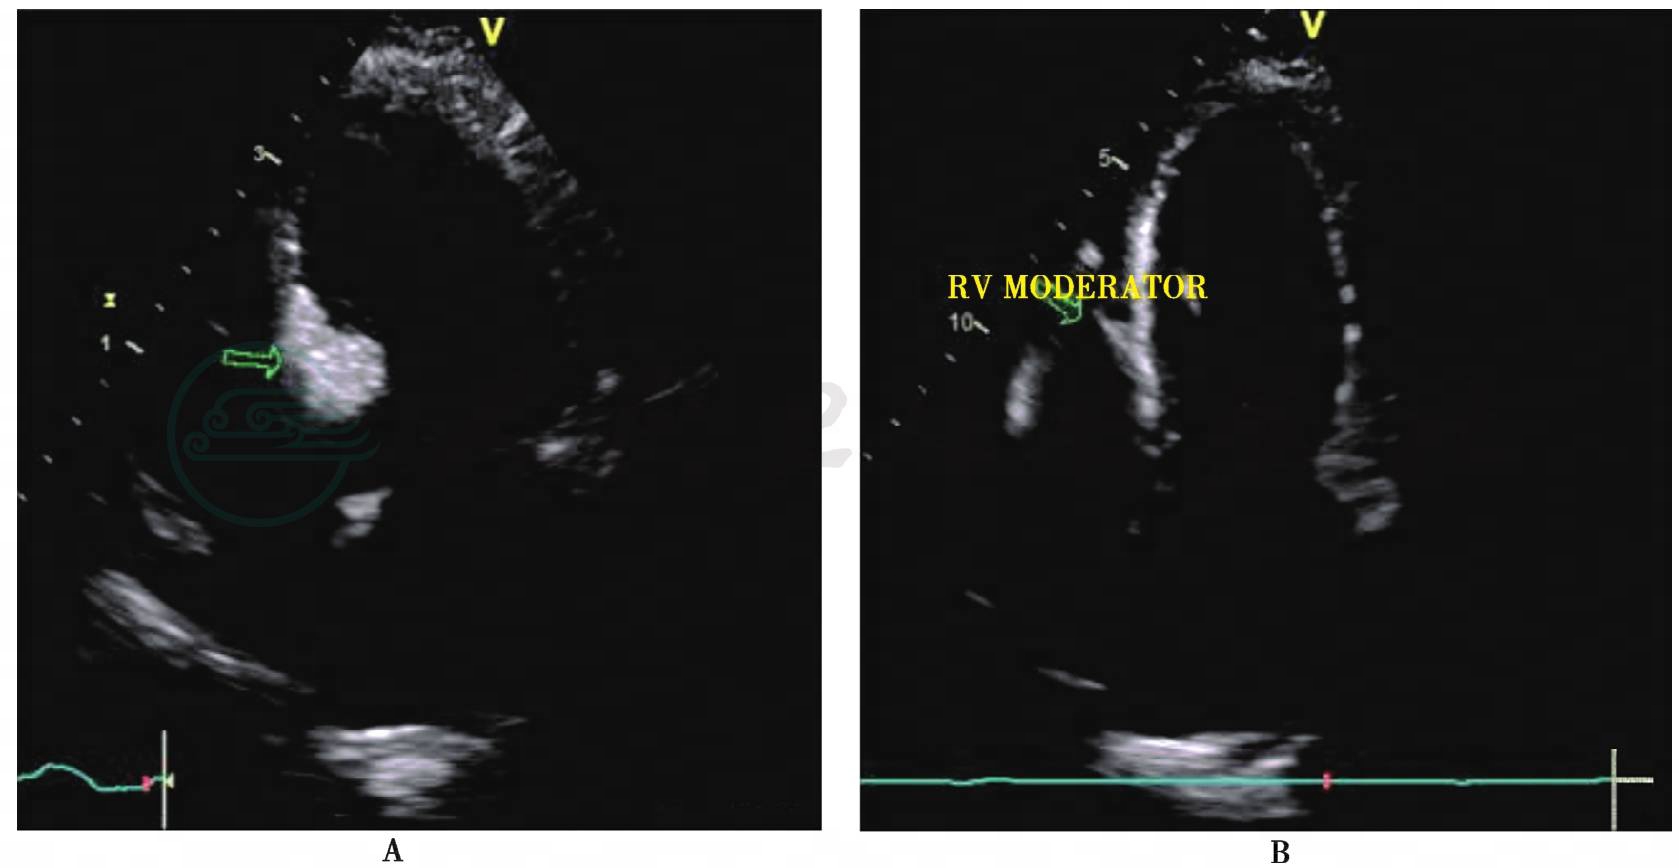

图6 室间隔基底段化学消融术中心肌声学造影

心尖四腔心切面示经第二间隔支注入声学造影剂后,室间隔基底段显影(图A箭头),随即部分右室调节束显影 (图B箭头)。经第三间隔支内注入造影剂后,乳头肌显影 (图C箭头)。RV moderator=右心室调节束;papillary muscle=乳头肌